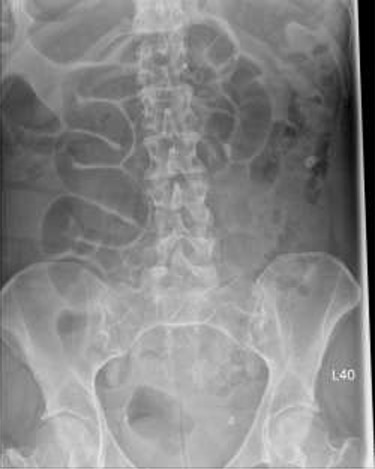

Patient initially diagnosed as biliary colic and surgical team had been contacted. Plain Abdominal radiograph showed dilated small bowels loops (Fig. 1). Chest radiograph revealed air under right hemi-diaphragm (Fig. 2). CT scan was done in emergency department and confirmed interposition of bowel between the diaphragm and the liver with a vascular/mesenteric pedicle swirl suggestive of malrotation or volvulus of the right colon. There was marked mural thickening and bold dilatation with high attenuation mucosa in keeping with closed loop obstruction and possible necrosis (Figs 3 and 4).